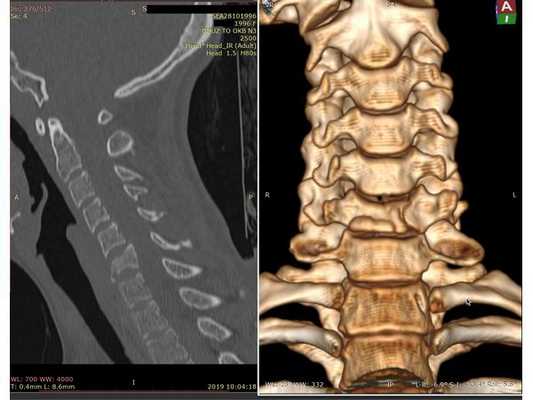

- Компьютерная томография шейного отдела позвоночника: выявлен компрессионно-оскольчатый перелом тела 6-го шейного позвонка (С6) и его дуги справа.

Контрольная КТ шейного отдела позвоночника на уровне тела позвонка С6. Виден установленный кейдж из пористого никелида титана и фиксирующая шейная пластина.